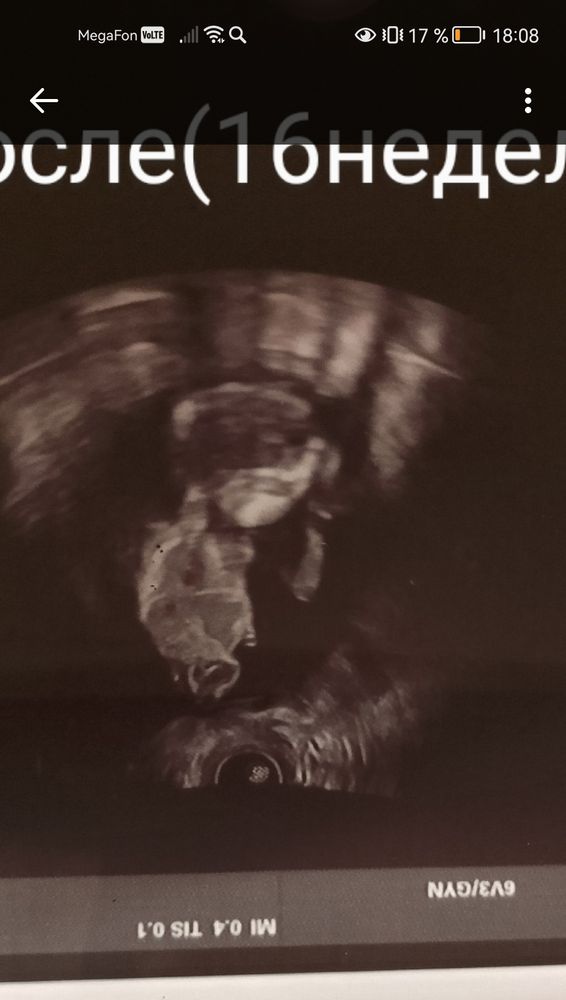

Мария в Благополучная беременность год Определение пола Пол малыша Девочки у подруги срок 16 недель как думаете видно кто будет или нет. Может кто понимает. 🤗 Посмотрите еще 20 записей на эту тему Отменить Ответить Солнце Вообще не понимаю где тут смотреть, как определили то, что девочка? 04.10.2024 Ответить Маргарита девочка 30.09.2024 Ответить Николь Девочка 30.09.2024 Ответить Мария Николь, а как определили? 30.09.2024 Ответить Ия Девочка 30.09.2024 Ответить Мария Ия, спасибо 30.09.2024 Ответить Доченька (как мы узнали) Девочки, как думаете, мальчик, девочка? Чаты Беременных Выберите чат: Январята-2026 Февралята-2026 Мартята-2026 Апрелята-2026 Майчата-2026 Июнята-2026 Июлята-2026 Августята-2026